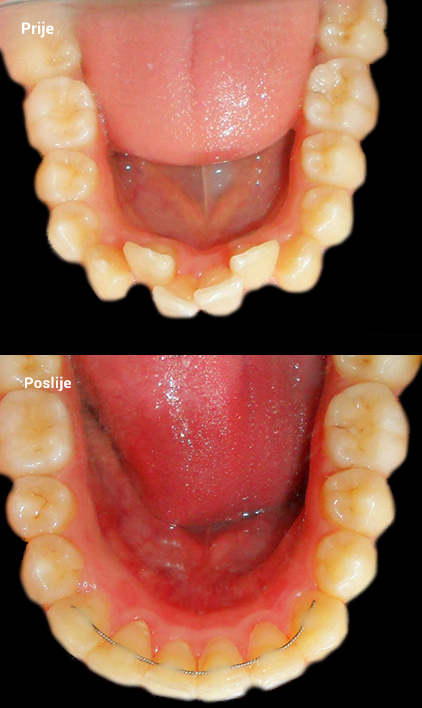

O našoj kvaliteti najbolje govore naši rezultati!